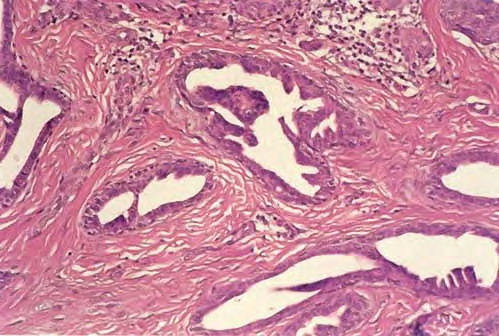

Tubular apocrine adenoma =غدوم مفترز انبوبي TUBULAR ADENOMA Epidemiology. Tubular adenomas are found in middle-aged adults as solitary, slowly growing, well-circumscribed nodules, situated mostly on the extremities. Black women appear to be preferentially affected. Etiology. The term tubular adenoma defines a group of benign appendage tumors histopathologically characterized mainly by numerous cystic, dilated, and branching […]